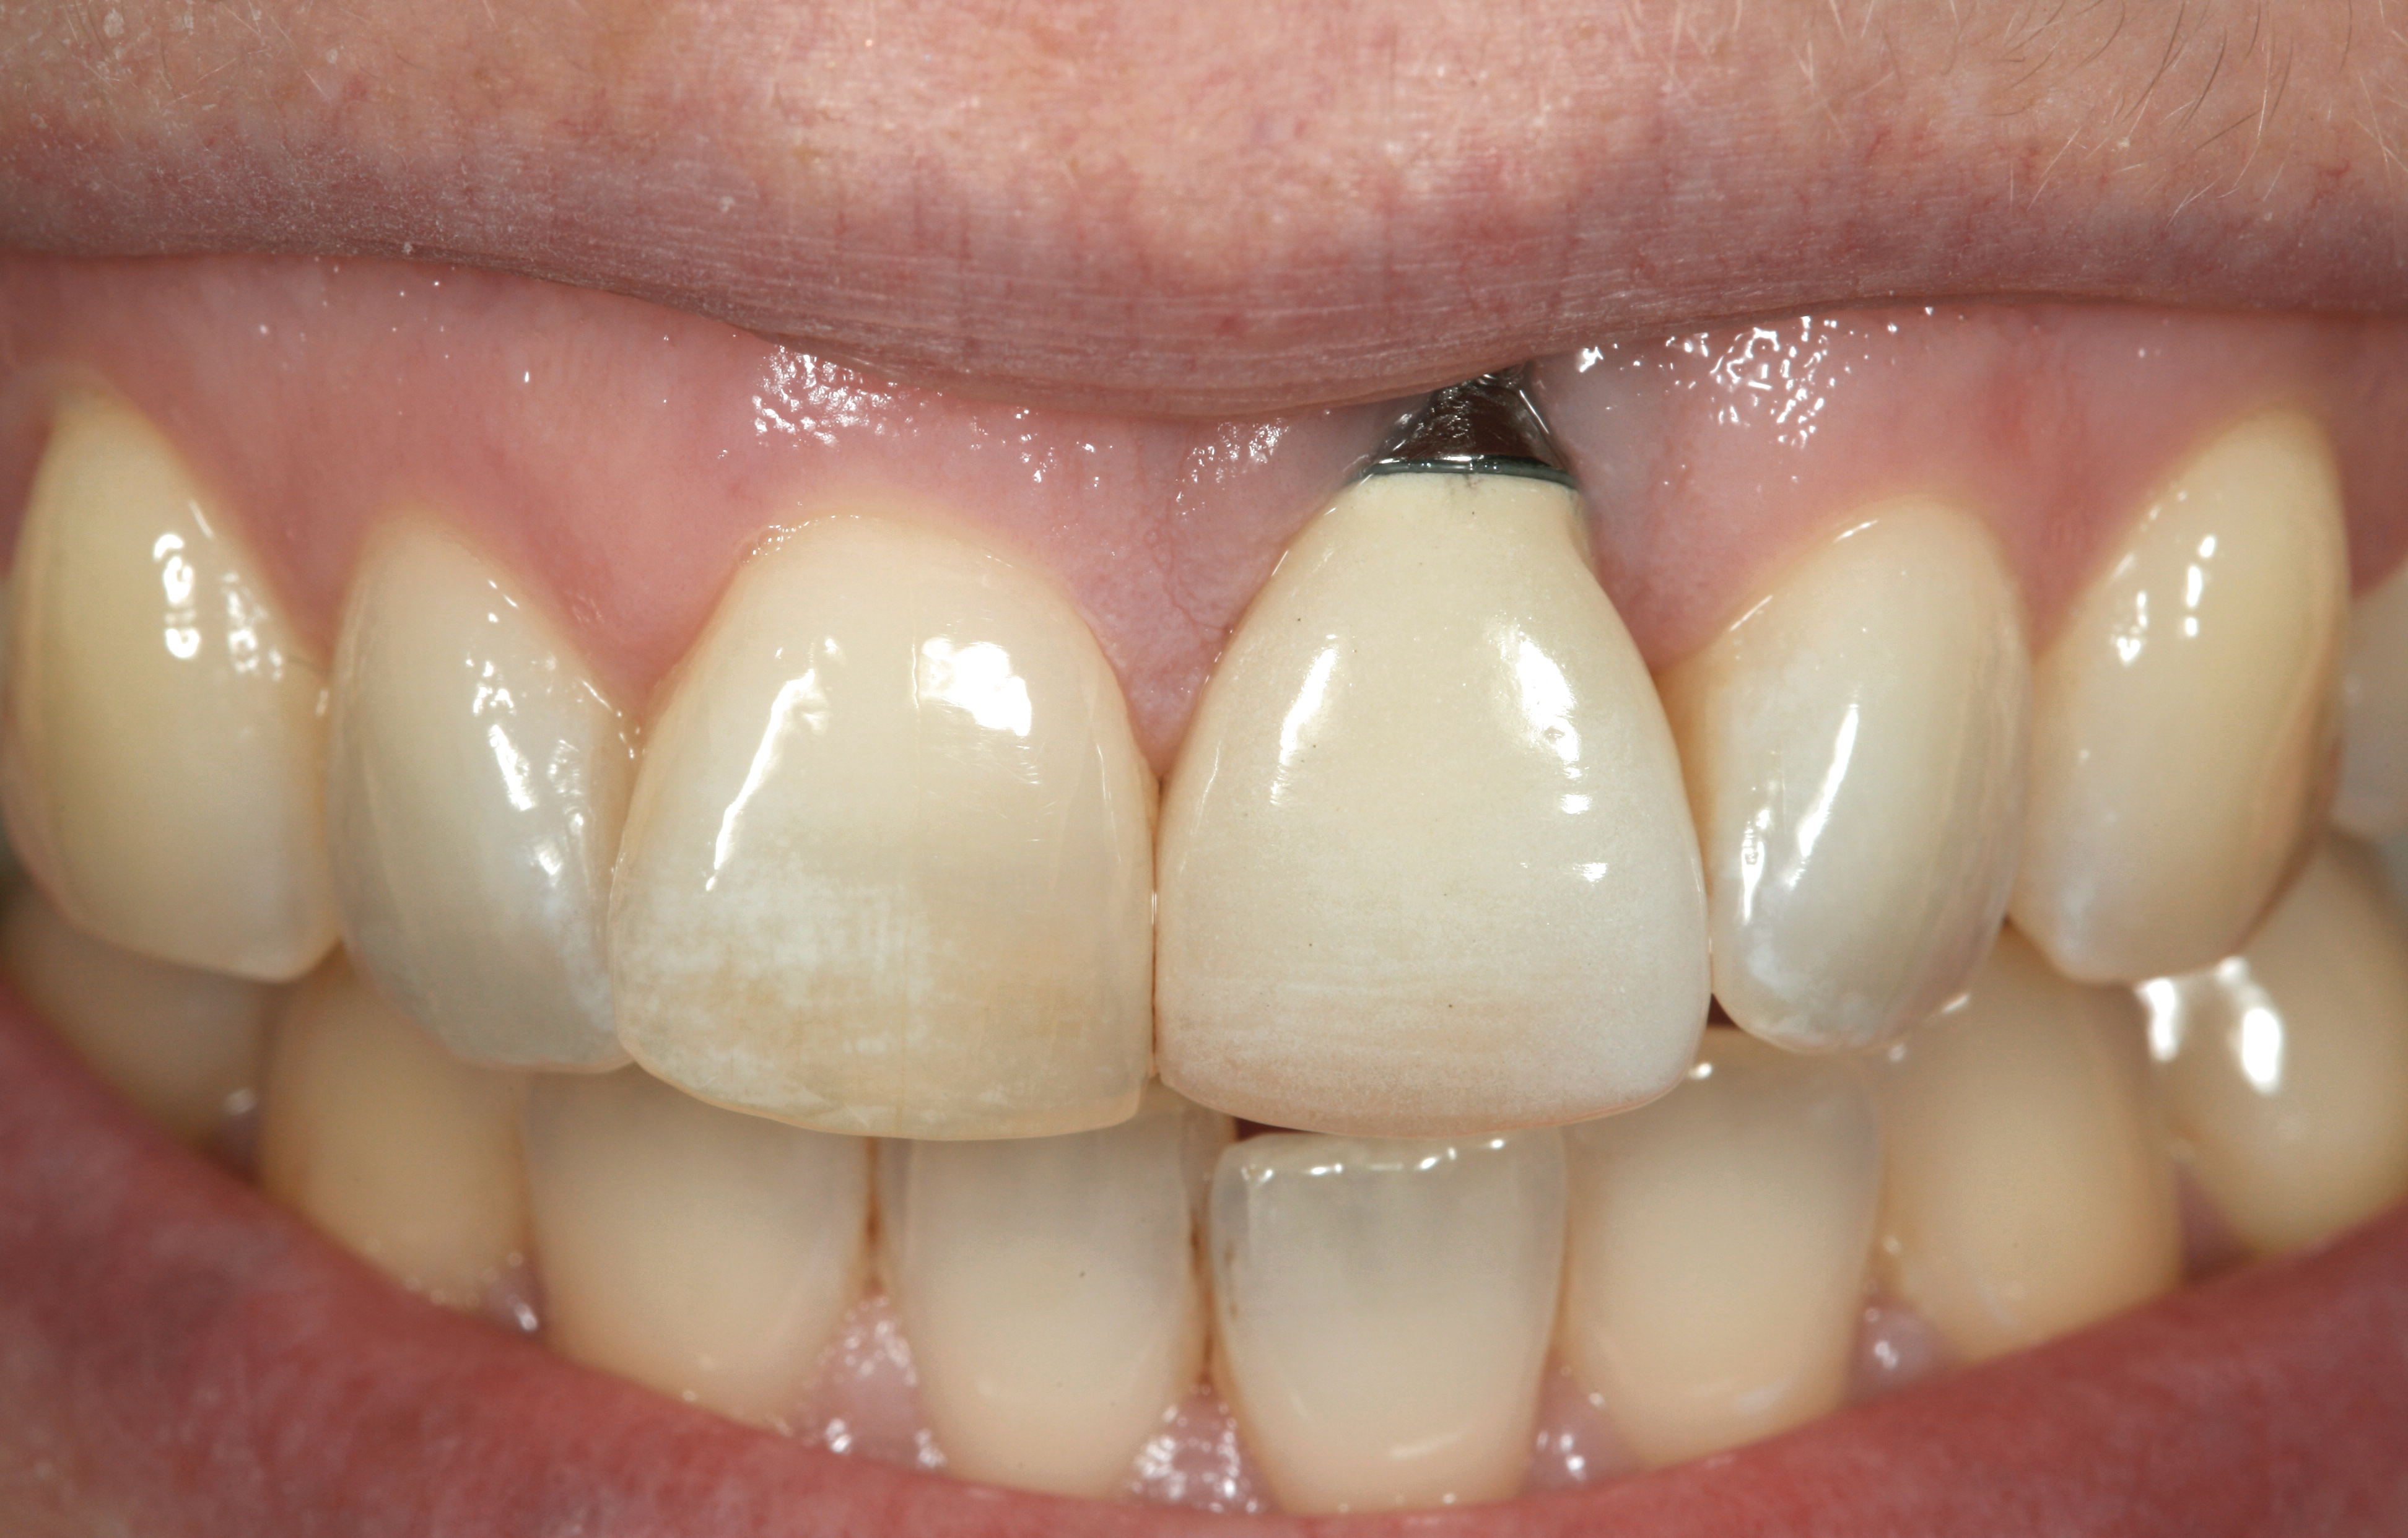

Problem: The implant is placed too facial with significant recession on the midfacial aspect of the abutment and/or crown; the implant is healthy and the patient has a high smile line with an intermediate to thick periodontal phenotype (Figure 1 and Figure 2).17-19

Problem: The implant is placed too facially, and there is significant labial gingival recession, contour change, and mucosal discoloration around the implant, abutment, and crown (Figure 3 and Figure 4). The implant attachment apparatus is intact and healthy, but the patient has a thin periodontal phenotype.

Fig 1. Midfacial recession can affect the esthetics of a smile and lead to an unsatisfactory outcome.

Fig 2. The cause for midfacial recession is excessive labial implant placement. Secondary to poor placement is overcontouring of the implant abutment.

Fig 3. A patient presented with a high smile line and midfacial recession of the maxillary right lateral incisor as evidenced by the increased tooth length compared with the contralateral lateral incisor.

Fig 4. Intraoral view of tooth No. 7 with the gingival zenith more apical than the adjacent central incisor and canine tooth.